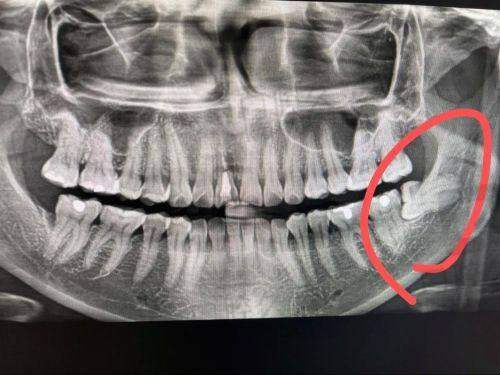

精细定位:借助数字化技术,医生能够清晰正确地了解智齿的位置、生长方向以及与周围组织的关系。就像在地图上精细标注目标一样,医生可以提前制定出更科学、更合理的拔牙方案,大大提高了拔牙的成功几率。